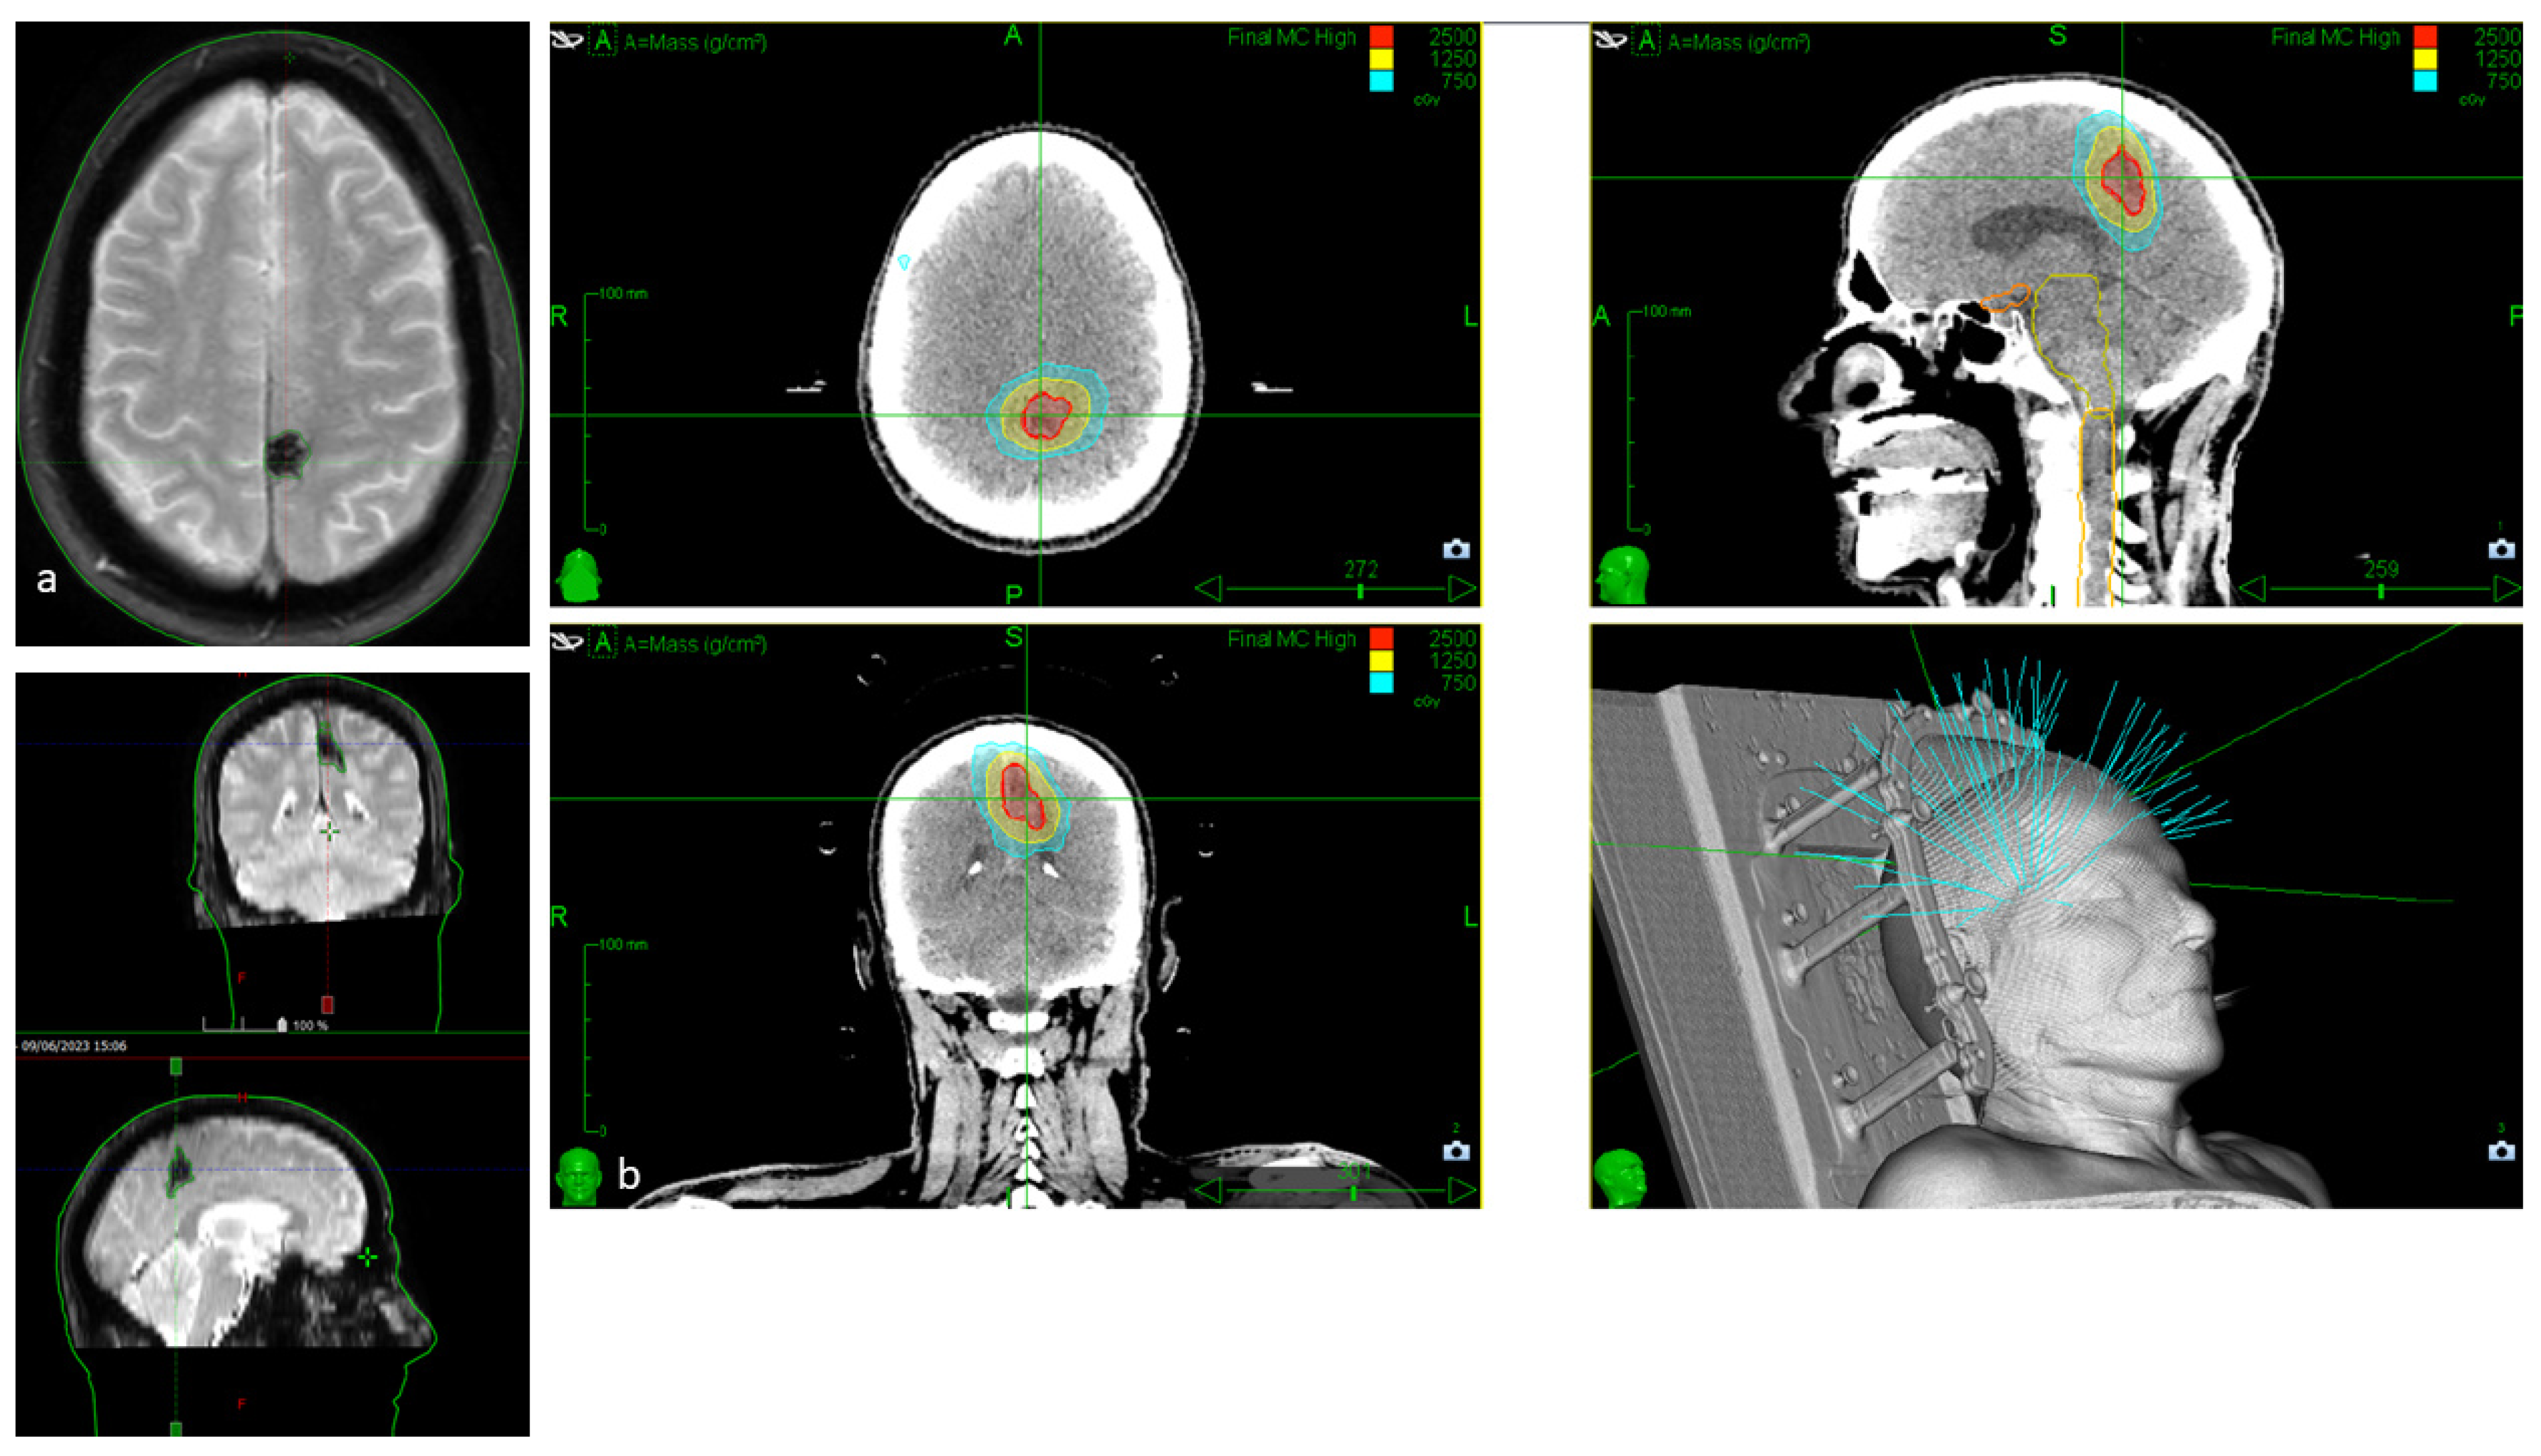

| Lesion Type | MRI Signal | Pathologic Features | Images |

|---|---|---|---|

| Type I | T1: hyperintense core T2: hyper- or hypointense core with surrounding hypointense rim | Subacute hemorrhage surrounded by a rim of hemosiderin-stained macrophages and gliotic brain | ![]() |

| Type II | T1: reticulated mixed signal core T2: reticulated mixed signal core with surrounding hypointense rim resulting in the “popcorn” appearance GE: low signal rim with blooming | Loculated area of hemorrhage and thrombosis of varying age, surrounded by gliotic, hemosiderin-stained brain; in large lesions, areas of calcification may be seen | ![]() |

| Type III | T1: iso- or hypointense T2: hypointense with a hypointense rim that magnifies the size of the lesion GE: hypointense with greater magnification than T2 | Chronic resolved hemorrhage, with hemosiderin staining within and around the lesion | ![]() |

| Type IV | T1: poorly seen or not visualized at all T2: poorly seen or not visualized at all GE: punctate hypointense lesions | Thought to be capillary telangiectasias | ![]() |